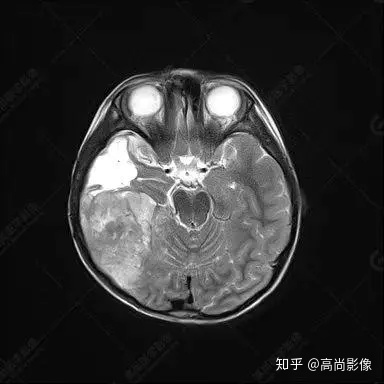

右側(cè)顳葉腫瘤切除術(shù)后(具體不詳):右側(cè)顳部骨質(zhì)不連續(xù)呈術(shù)后改變,右側(cè)顳葉術(shù)區(qū)見片狀長(zhǎng)T1長(zhǎng)T2信號(hào)影,F(xiàn)LAIR呈低信號(hào);術(shù)區(qū)后方右側(cè)顳枕葉見一巨大占位性病變影,邊界欠清,大小約6.2×5.8×4.3cm(前后×左右×上下),信號(hào)不均勻,T1WI呈等稍低信號(hào)間雜少許高信號(hào),T2WI呈高稍低混雜信號(hào),DWI示部分病灶彌散受限,相應(yīng)ADC圖減低,磁敏感序列見部分呈極低信號(hào),增強(qiáng)掃描可見明顯不均勻強(qiáng)化,鄰近硬腦膜及小腦幕增厚并明顯強(qiáng)化;另延髓右前方及右側(cè)橋小腦角區(qū)見一不規(guī)則形異常信號(hào)影,大小約3.2×1.3×3.7cm(左右×前后×上下),呈長(zhǎng)T1稍長(zhǎng)T2信號(hào),F(xiàn)LAIR呈等信號(hào),DWI未見受限,增強(qiáng)后明顯均勻強(qiáng)化,鄰近腦膜明顯強(qiáng)化。鄰近腦實(shí)質(zhì)及右側(cè)顳角明顯受壓;左側(cè)大腦半球未見局灶性信號(hào)異常,中線結(jié)構(gòu)稍左移。

右側(cè)顳葉腫瘤切除術(shù)后:現(xiàn)術(shù)區(qū)后方右側(cè)顳枕葉及延髓右前方占位,右側(cè)顳枕部硬腦膜及小腦幕明顯強(qiáng)化,結(jié)合既往影像資料,考慮為胚胎源性惡性腫瘤,如非典型畸胎樣/橫紋肌樣瘤(AT/RT)或原始神經(jīng)外胚層腫瘤(PNET)。

非典型畸胎樣/橫紋肌樣瘤(AT/RT) 是一種高度惡性中樞神經(jīng)系統(tǒng)腫瘤,臨床罕見,臨床表現(xiàn)無(wú)特異性,好發(fā)于 5 歲以下兒童,尤以 3 歲以下多見,在兒童原發(fā)性中樞神經(jīng)系統(tǒng)(CNS)腫瘤中占 1%~3%。該腫瘤體積一般較大,幕上大于幕下,有明顯的占位效應(yīng)。該腫瘤成分復(fù)雜,囊變、出血、壞死常見。因此 AT/RT信號(hào)混雜,囊性部分呈 T1WI低、T2WI高信號(hào),增強(qiáng)后不強(qiáng)化;若瘤體出血,囊內(nèi)可見T1WI稍高信號(hào)、T2WI低信號(hào),實(shí)性部分在 T1WI上呈混雜等、低信號(hào),在T2WI 及 T2-FLAIR上呈混雜等高信號(hào),增強(qiáng)掃描后大部分呈環(huán)形條帶樣明顯強(qiáng)化,中心壞死區(qū)不強(qiáng)化。另外,該腫瘤實(shí)性成分在DWI上呈高信號(hào),說(shuō)明腫瘤細(xì)胞核密集,水分子擴(kuò)散明顯受限,提示該腫瘤惡性程度高,容易復(fù)發(fā)及轉(zhuǎn)移。